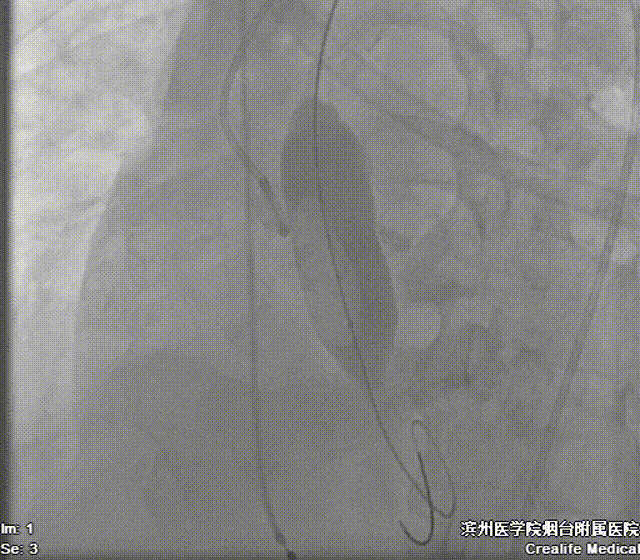

术前测量,患者主动脉峰值流速452cm/s,平均跨瓣压差36mmHg,术中通过患者左侧锁骨下动脉建立辅入路,造影示主动脉根部明显钙化,左室内中量反流影像。

22mm球囊预扩影像示双侧冠脉灌注良好,无明显腰征,决定植入AV26号瓣膜。

造影辅助下精准释放

造影,超声示微量瓣周漏,术后平均跨瓣压差5mmHg,主动脉血流峰值流速1.7m/s,患者血流动力学指标显著改善。